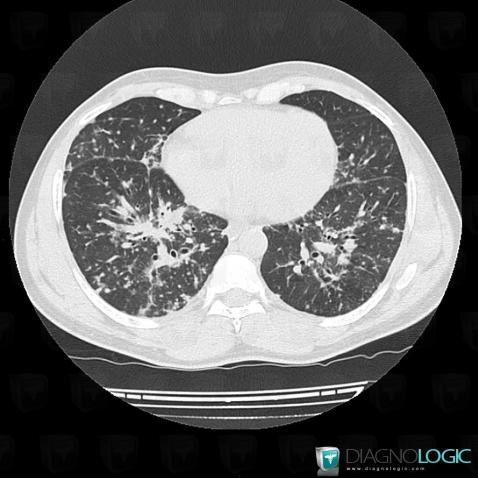

Sarcoïdose, Parenchyme pulmonaire, Scanner

Voici les informations spécifiques à l'image clé ci dessus:

- Diagnostic Sarcoïdose, Localisation(s) Parenchyme pulmonaire, comportant les gammes Maladie prédominant en péri hilaire, Condensation alvéolaire localisée, Condensation alvéolaire chronique